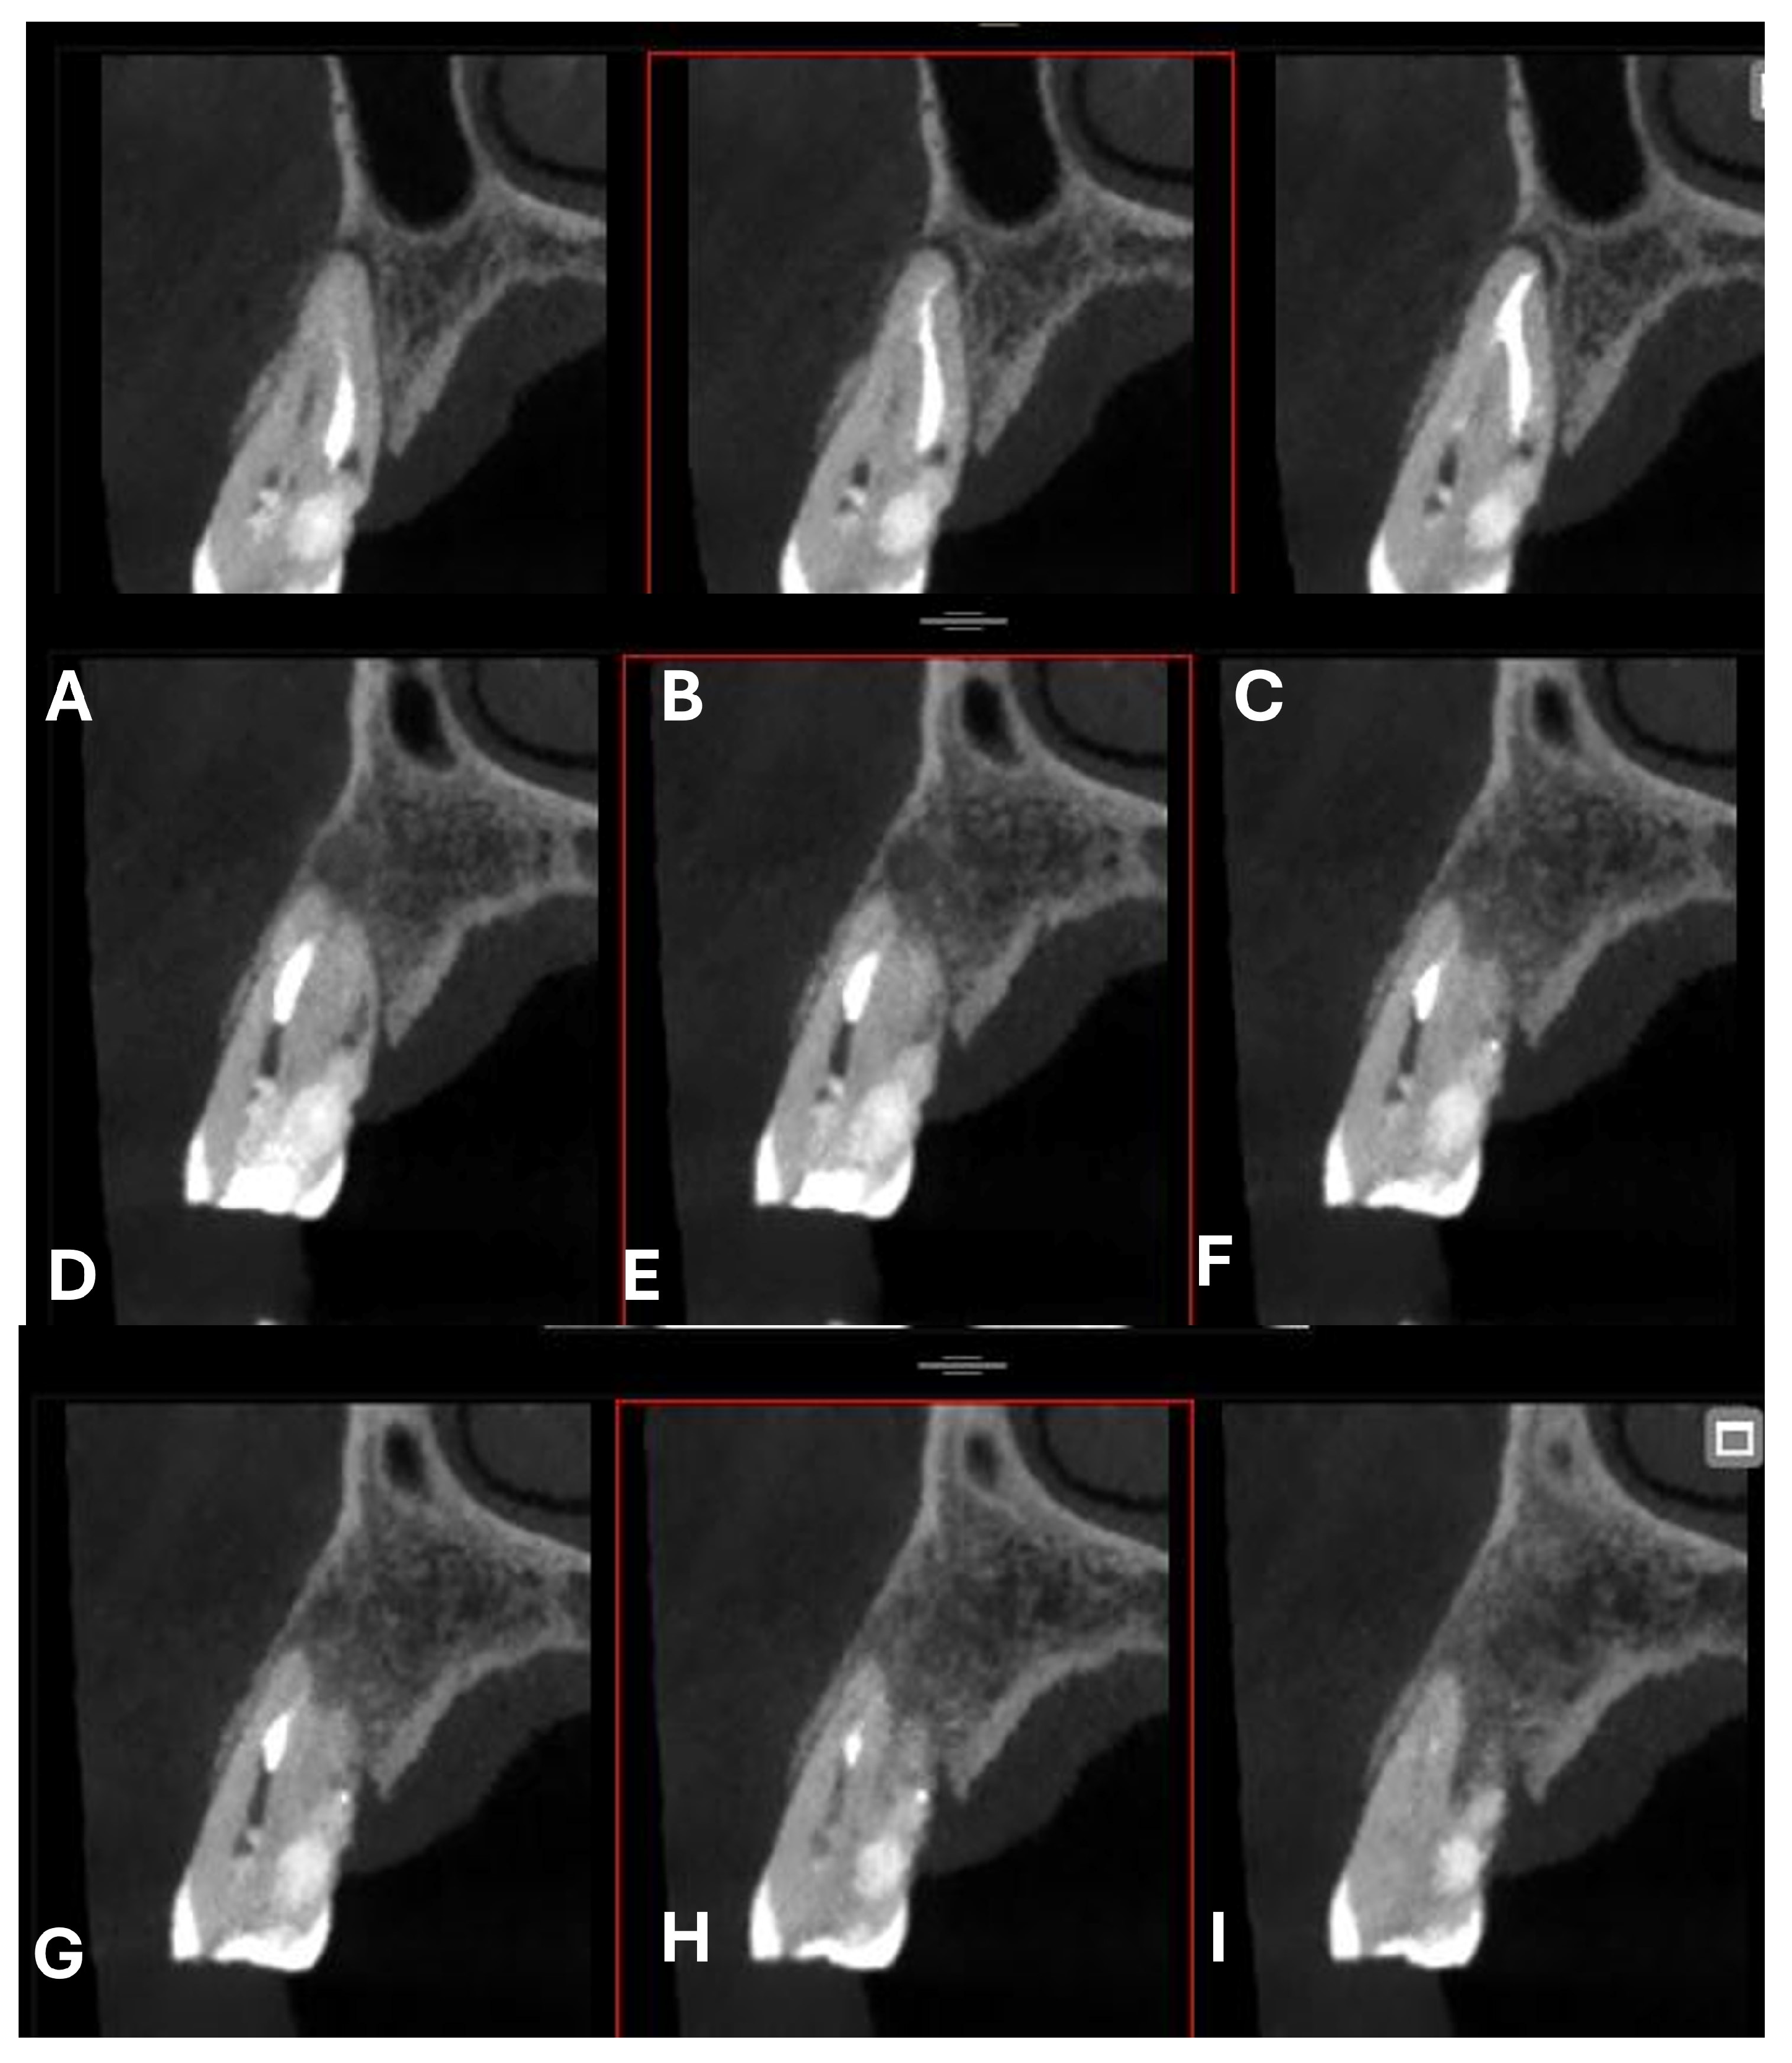

Figure 2.

Axial CBCT images of tooth 1.4, showing its ECR and PL. (A–E) Sequential scrolling on the axial plane from the cervical area to the middle third of the root; (F,G) Segmentation of Figure 2E using the advanced software functions iRYS® (MyRay, Imola, Italy); (H,I) Sequential scrolling on the axial plane of the apical third of the root, including the PL.

A CBCT examination (X9 Pro®, MyRay, Imola, Italy), performed with dedicated field of view (FOV) (6 × 6) and exposure parameters, was essential for accurate diagnosis and treatment planning. This device optionally features a specific Booster function for users with advanced expertise, which allows for further customization of exposure parameters to optimize the examination more effectively. Optimal management of the FOV, properly centered and limited to the anatomical area of interest, in this specific case slightly extended (6 × 6) to clearly rule out a possible involvement of the maxillary sinus in agreement with the attending otorhinolaryngologist, enabled the acquisition of broader and more detailed clinical and diagnostic information, which is essential in endodontics. Moreover, it allowed for a significant reduction in radiation dose while optimizing spatial resolution [22]. The imaging clarified the extent of the resorption and defined its perimeter, demonstrating an endodontic-periodontal communication, classified as 3Bp according to Patel’s classification [21] (Figure 2, Figure 3, Figure 4 and Figure 5).